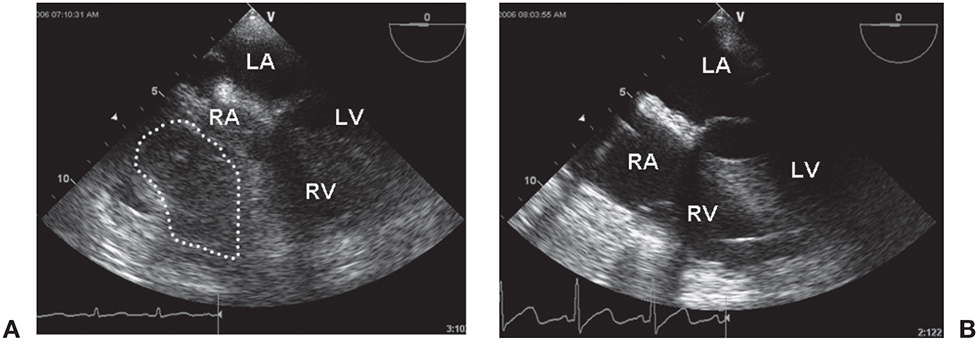

Figure 12.2.: Acute Regional Pericardial Effusion: Right Atrial Compression.

Acute regional pericardial effusion: right atrial compression. The heart is viewed in the midesophageal four-chamber view. A. A loculated pericardial clot (dotted line) is seen around the right atrium (RA), almost obliterating its cavity and partially compressing the right ventricle (RV). B. The same heart following decompression is seen. LA, left atrium; LV, left ventricle.